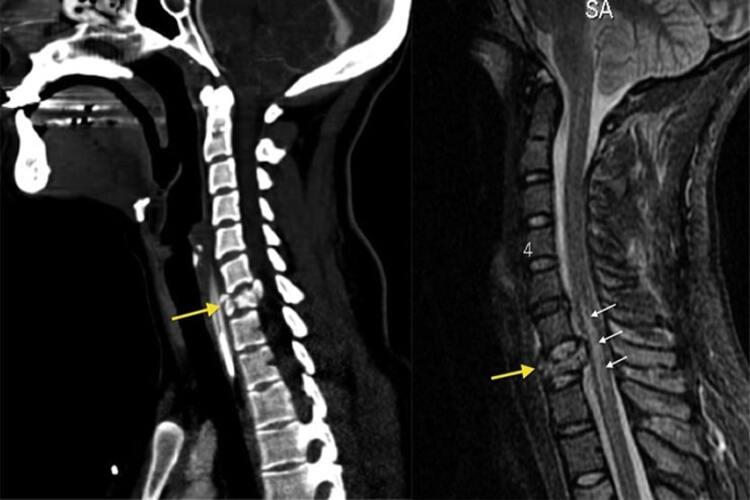

تشخیص شکستگی مهره گردن، بر اساس یافتههای رادیولوژیک و علائمی مانند محدودیت حرکت و درد در گردن است. پزشک از تصویربرداری با اشعه ایکس، برای تشخیص کمک میگیرد. در برخی موارد برای تأیید تشخیص یا ارزیابی میزان آسیب، ممکن است نیاز به انجام MRI یا CT Scan باشد.

- CT Scan ستون فقرات: این روش برای تأیید تشخیص، ارزیابی شدت شکستگی و آسیب واردشده به مهره گردنی انجام میشود.

- MRI: MRI یک اسکن دقیق است که از یک میدان مغناطیسی برای ایجاد تصاویر کاملی از استخوانها و بافتهای نرم گردن استفاده میکند. از این روش هم برای تأیید تشخیص و ارزیابی شدت آسیب کمک گرفته میشود.